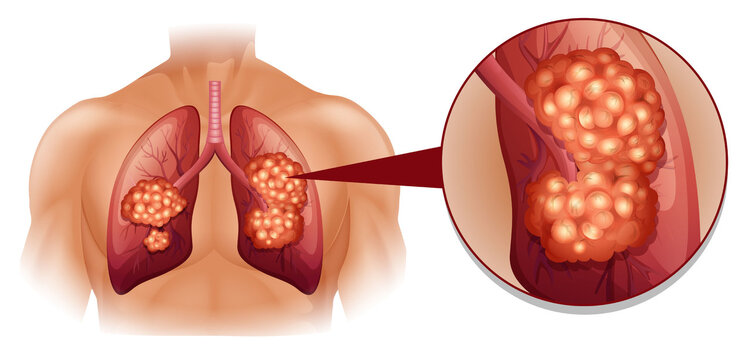

肺癌图片与正常肺图片[b0]肺部肿瘤是指发生在肺部的异常新生物分为良性肿瘤和恶性肿瘤两大类[b1]肺肿瘤和肺癌的图片肺癌长在肺叶上吗左肺囊肿是什么意思七七岁肺癌[b2]微创介入显身手不开刀消灭肺肿瘤[b3]全网资源[b4]肺肿瘤的恶性程度不能单凭大小判断[b5]肺肿瘤5cm良性几率多大当得知肺肿瘤长到5cm这样的尺寸时患者的内心[b6]老年男性右上肺结节大小16厘米手术明确浸润性腺癌老[b7]中央型肺部鳞状肿瘤能否实现治愈[b8]肺鳞癌术后复发[b9]肺上长了肿块不一定都是肺癌75岁女性2月来胸闷当地[b10]肺部病灶通过立体定向放疗之后这个肿瘤一个月之后复查已经消失了[b11]肺腺癌知多少一文带你揭秘这个肺事[b12]肺早期肿瘤究竟有多大一文读懂[b13]肺癌恶化最快的三种癌是什么肺癌是肺部的一种恶性肿瘤疾病这种疾病[b14]就是我们超过5个厘米以上的这个肺部的肿瘤我们可以先通过微创介入[b15]肺上长了肿瘤并不意味着无药可救哦首先要明确肿瘤的性质是列栽[b16]一个53岁肺腺癌晚期的病例[b17]拒绝化疗选择精准微创[b18]纵隔肿瘤严重吗是不是癌症[b19]面对体检报告上的肺结节10mm很多人心中都会升起一丝担忧这个[b20]右肺两个恶性肿瘤病人不能趴着只能躺着穿刺针刚刚好微[b21]左肺巨大肿瘤的临床决策思路分享[b22]肺部肿瘤知多少良恶性质大不同[b23]肺上有肿瘤是什么病严重吗[b24]年初手术成功实施粒子精准覆盖肿瘤区域[b25]肺鳞癌知多少一文带你全面了解[b26]肺早期肿瘤大小有讲究[b27]我院这位住院患癌的患者是得了周围型的肺部患癌而且肿瘤还侵犯[b28]6mm的肺结节在影像学上是一个相对较小的发现可能是良性的也可能[b29]患者胸背疼一个月做了ct发现肺上大肿块病理为浸润性肺腺癌[b30]5个层面讲清楚肺癌医学科普[b31]肺小结节和大肺癌有很大的区别[b32]6厘米有肺血管穿行图1并且血管有增粗[b33]肺结节是肺部影像学上的一种表现可能由炎症感染良性肿瘤等多种[b34]肺结节与肺癌的关系别再被误导了[b35]这类肺结节基本不复发[b36]得了肺癌要科学治疗这位老大伯用药两次肿瘤明显缩小家人[b37]简述常见良性肺肿瘤及其影像学特点[b38]一个不起眼的肺结节长成一个大肿瘤其实是很[b39]肺腺癌和肺鳞癌到底有哪些区别[b40]肺部鳞状细胞癌的一般存活年限是多少肺部鳞状细胞癌是一种非小细胞[b41]不开刀消灭肺肿瘤微创介入治疗快准狠[b42]患者因为胸痛就诊河津市人民医院行ct检查发现肺上长了个肿瘤[b43]瑞金胸外病例拾萃10肺类癌的诊治[b44]肿瘤2点5公分肺癌属于几期当发现肺部有一个2[b45]肺癌ct影像全解析带你读懂肿瘤信号[b46]重燃患者生命之光山东省第二人民医院肿瘤内科联合多学科精准施治肺巨[b47]12mm肺结节是肺癌几期你了解多少[b48]2cm部分实性结节恶性张力高病理浸润性肺癌磨玻璃[b49]肺结节的原因多种多样可能是由感染炎症良性肿瘤恶性肿瘤等导致[b50]202487天津医科大学总医院肺部肿瘤外科副主任医师[b51]肺结节和钙化灶是肺癌的前兆吗[b52]肺鳞癌是什么癌症[b53]2024516天津医科大学总医院肺部肿瘤外科副主任医师[b54]1肿块体积显著增大晚期肺癌的肿瘤体积[b55]肺结节癌变前可能出现的6种表现抖出健康知识宝藏[b56]肺结节早期肺癌一文解读肺部ct报告[b57]肺癌是恶性肿瘤疾病随着病情的发展可能会导致癌细胞出现远处转移[b58]1厘米的肿瘤[b59]